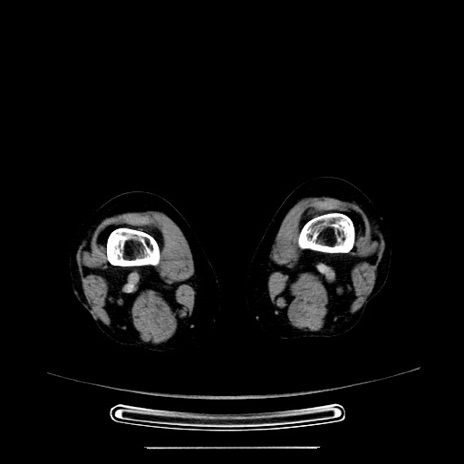

症例5(横断像)

【症例】70歳代女性

【主訴】お腹が張る

【現病歴】1週間くらい前から腹部膨満の自覚あり。昨日夜から増悪したため、本日救急外来受診。

【身体所見】意識清明、BT 36.5℃、BP 165/106mmHg、HR 80bpm、SpO2 98%、腹部:膨満、軟、自発痛・圧痛なし、触診にて不快感あり、腸蠕動音:減弱

【データ】WBC 12600、CRP 1.04